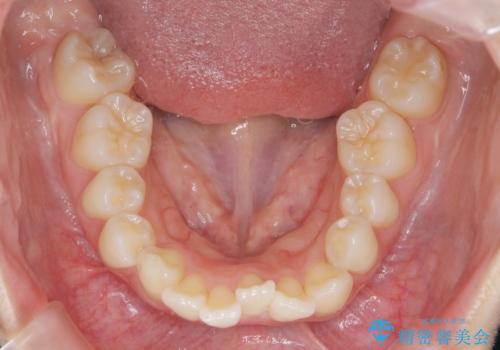

- 5年前にワイヤー矯正治療を終了したが、突き出たように見える前歯の仕上がりが気に入らず、再矯正治療を希望され来院されました。

マイクロインプラントを用いた遠心移動とIPRを行うことによる前歯の突出感の改善をマウスピース矯正治療で計画します。

突出していた前歯の角度が大きく改善し、審美的な仕上がりに満足いただくことができました。